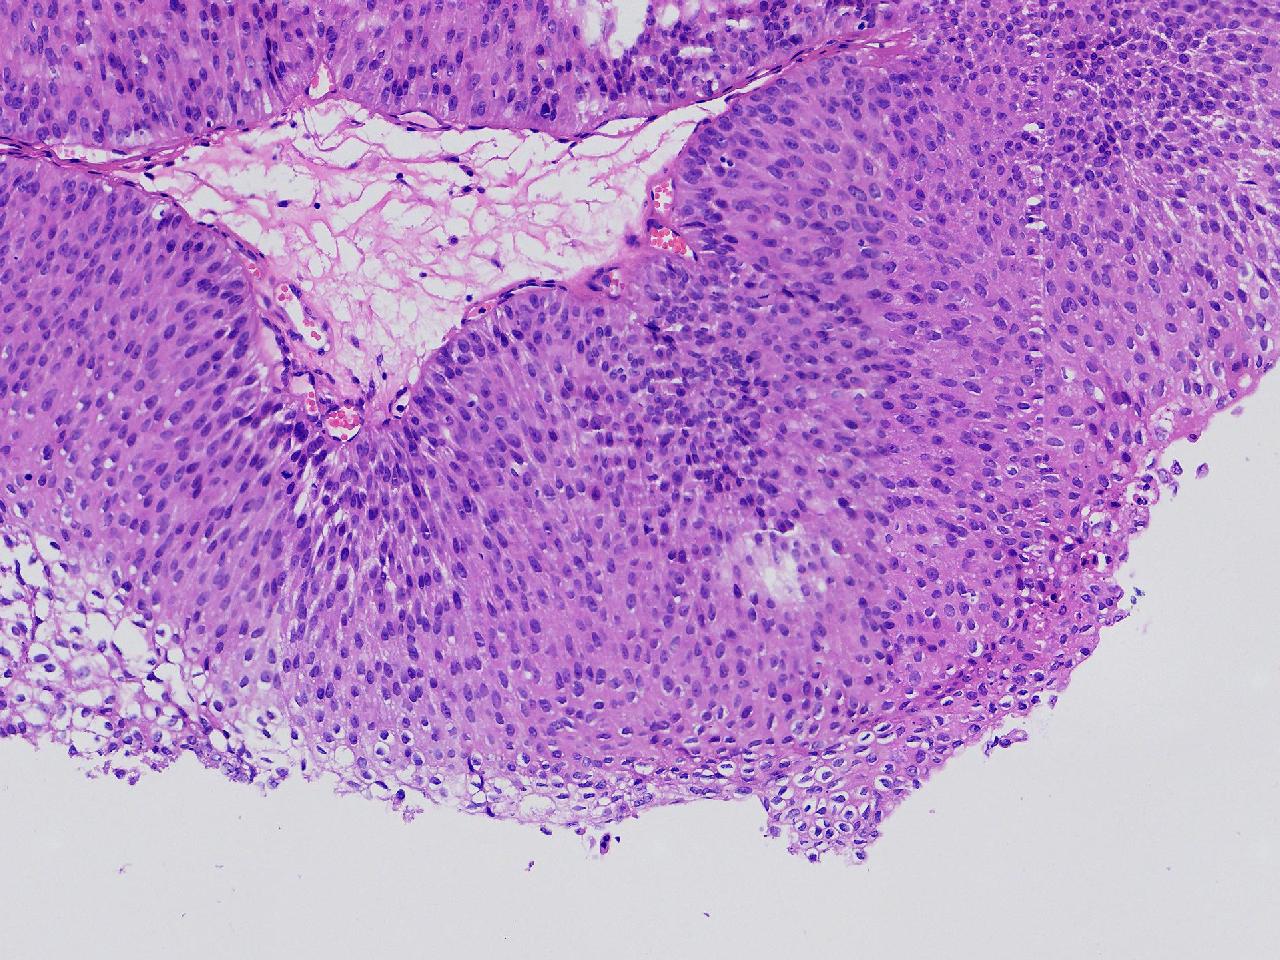

男,79岁,膀胱肿物。

膀胱肿物

灰白色不整形软组织多块,2X1X1厘米。

考虑:乳头状尿路上皮癌

考虑低级别,非浸润。

乳头状尿路上皮癌,低级别。

这几张图片上没有看到明确的浸润。